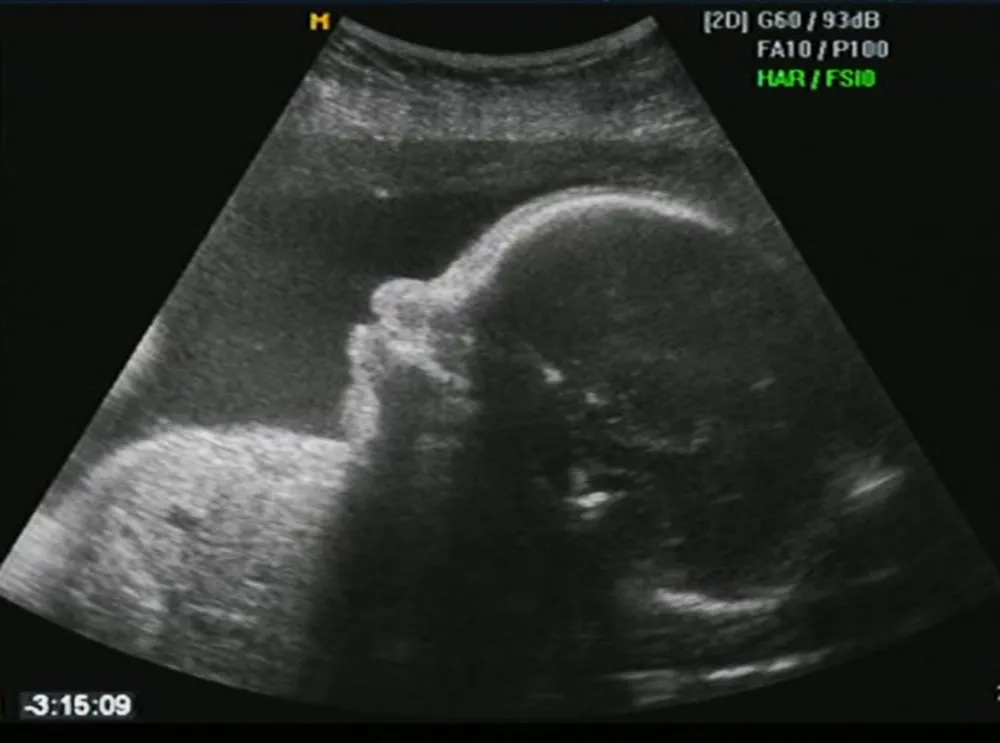

2. Hình ảnh siêu âm thai 27 tuần

Các chỉ số sinh trắc của thai nhi 27 tuần cụ thể như sau:

- Đường kính lưỡng đỉnh (BPD): 62-75mm

- Chiều dài xương đùi (FL): 46-55mm

- Chu vi vòng đầu (HC): 234-273mm

- Chu vi vòng bụng (AC): 206-253mm.